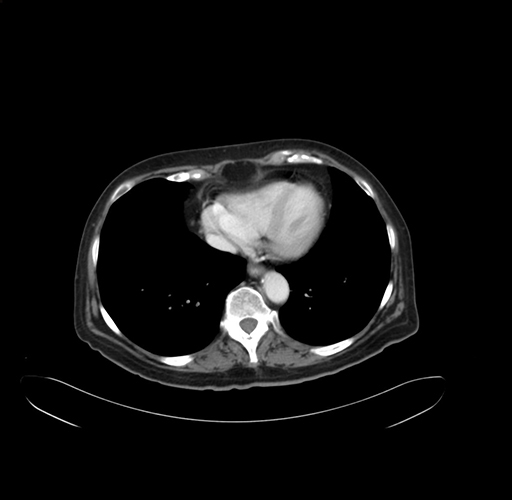

Pre-Chemo: Axial Venous

Axial Venous